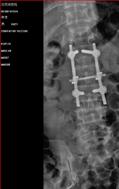

脊柱创伤、退变——开展颈椎骨折椎体次全切除植骨内固定,胸、腰椎压缩骨折椎弓根钉内固定,椎管狭窄减压手术,总结积累脊柱创伤有效治疗方法。

1).腰2椎体压缩约2/3术前、 术后

2).腰5滑脱 术前、 术后